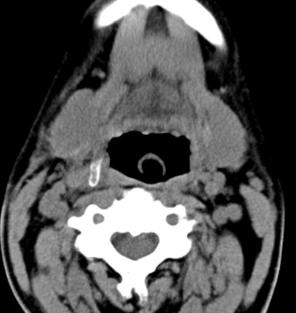

标题: CT17168:会诊,颈部包块 [打印本页]

标题: CT17168:会诊,颈部包块

怎么不传病史呢?右侧颌下腺炎症?

考虑:右侧颌下腺炎症。建议强化。

不排除右侧颌下腺恶性肿瘤可能;建议行进一步检查。

考虑:右侧颌下腺炎症可能。

我也是报的颌下腺炎症。